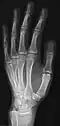

- Hand - DP and Oblique

-

Left hand by dorsoplantar projection -

Lateral projection -

Oblique projection